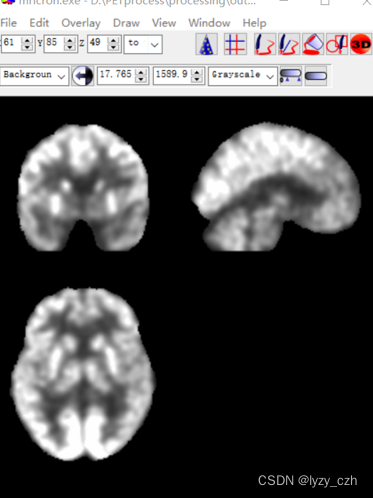

打开output图像如下:

最后得到的图像如下:

这便是PET预处理后的图像,到此整个PET预处理流程已经走完,做完后发现这也太复杂了,如果要处理几百张图像人估计都没了。。。所以接下来的才是重头戏,批量预处理。